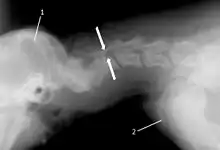

T2 weighted MRI in neutral (A) and linear traction (B) of a seven-year-old Doberman with a two-year history of cervical pain treated with NSAIDs and presented acutely tetraplegic: A C6-C7 and C5-C6 traction responsive myelopathy are evident on MRI. The spinal-cord hyperintensity seen at the C5-C6 is suggestive of chronic lesion and most likely responsible for the chronic history of cervical pain, while the C5-C6 lesion was most likely responsible for the acute tetraplegia.

Same dog (A) treated with double implant (B) three days after surgery: The dog became ambulatory three days after surgery. Four weeks after surgery, it had ataxia without conscious proprioceptive deficits, and three months after surgery, the dog was neurologically normal. The owner reported it had been two years since the dog was able to hold its neck in an elevated position.